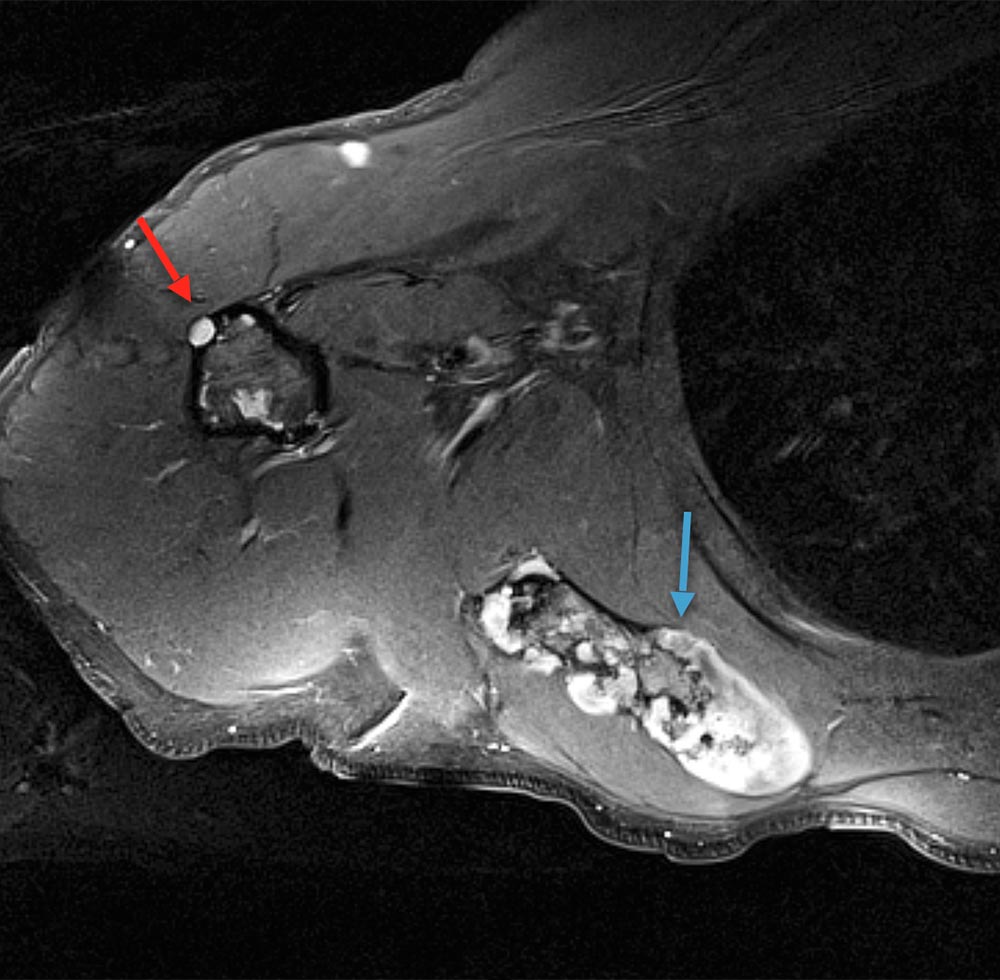

Das Maffucci-Syndrom ist charakterisiert durch multiple Enchondrome, oft sichtbar als umschriebene derbe Auftreibungen an Fingern und/oder Zehen in Kombination mit Spindelzell-Hämangiomen. Synonym: Enchondromatosis Ollier-Maffucci.

Der Überwuchs beim Maffucci-Syndrom ist gekennzeichnet durch prallelastisch-derbe, indolente, einem Knochen zuzuordnende, aus dysplastischem Knorpelgewebe stammenden Auftreibungen (Enchondrome). Diese können uni- oder bilateral, aber meist deutlich asymmetrisch vorliegen. Durch die Enchondrome kann es, je nach Lokalisation, zur Wachstumsreduktion und Verkrümmung betroffener Gliedmaßenabschnitte kommen. Am häufigsten sind Unterarme und Unterschenkel, oft aber auch Hände und Füße betroffen.

Enchondrom-Herde können bis zur Adoleszenz auftreten, danach i. d. R. kein Neuauftreten, vielmehr Restitution berichtet. Eine maligne Entartung von Enchondromen zum Chondrosarkom kann im Erwachsenenalter vorkommen, das Entartungsrisiko wird mit maximal 25 % angegeben.